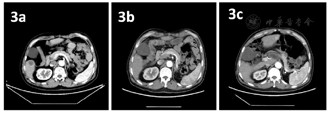

2021年9月11日胸腹平扫+增强CT提示:(1)食管癌治疗后,请结合临床及老片;(2)考虑右肺放疗后改变,右下肺结节较2021年7月22日片明显缩小;右侧胸膜增厚;(3)升主动脉增粗,主动脉及冠状动脉粥样硬化;(4)右肾小囊肿,右肾结石;(5)左肾未见明显显示,左肾上腺结节、腹腔及腹膜后结节、左胸壁皮下结节及肝右叶异常强化影,较前片2021年7月22日片相仿(图1,图2,图3)。